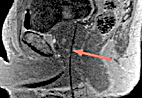

Pre-procedure MRI confirms placement of applicator in the target tissue.

The thin (1.6mm) laser fiber is then placed into the tumor through the rectum, under MRI guidance. The laser is activated to begin heating of the tumor. Using MR images and special software allows the physician to see the tissue heating during laser irradiation, and to control how much energy is delivered.